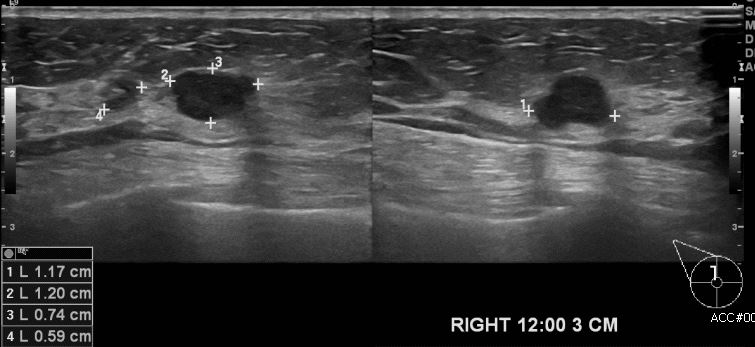

상기환자 우측 유방에 만져지는 멍울로 내원하신 70대 여성 분으로 우측

12시 방향에서 3cm 떨어진 거리의 만져지는 멍울 조직검사 시행하여 우측 침윤성 유관암 진단되었습니다.